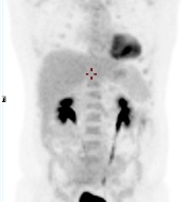

TEP-FDG masse médiastinale hypermétabolique isolée